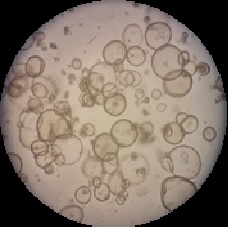

Within the framework of the fellowship, a human intestinal organoid biobank was successfully established, including seven lines originated from biopsies obtained in screening colonoscopies and fourteen lines derived from tissue pieces obtained during colorectal surgery.

Organoids derived from human colon crypts (Laura Valle's Lab)